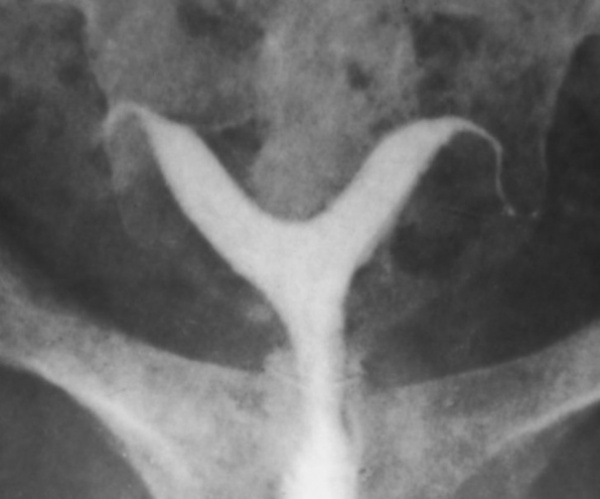

· микционная цистоуретрография – для определения состояния нижних мочевых путей (по показаниям);

· МРТ органов малого таза – для исключения патологий органов половой и мочевыводящей систем (по показаниям).

Пороки развития матки выявляется, как правило, случайно. О наличии врожденной патологии женщина может не догадываться. При выраженной деформации дна матки нередко наблюдается первичное бесплодие, которое и заставляет пациентку обратиться к врачу. Стандартное гинекологическое исследование при седловидной и двурогой матке малоинформативно. В диагностике врожденных аномалий матки решающая роль отводится инструментальным исследованиям – УЗИ органов малого таза, гистероскопии, гистеросальпингографии, магнитно-резонансной томографии (МРТ). При обнаружении порока для восстановления нормальной анатомии матки применяется хирургическое лечение. После исправления врожденного дефекта шансы зачать и выносить малыша резко увеличиваются.

Несмотря на то, что возникновение данного порока обусловлено генетической предрасположенностью, женщины с такой патологией имеют типичный набор хромосом (46, XX). У них правильно сформированы наружные половые органы, развиты вторичные половые признаки, имеются нормальные яичники. Заболевание характеризуется аменореей, половая жизнь становится невозможной. При осмотре выявляют полное отсутствие или недоразвитие влагалища и нередко матки. Для окончательного установления диагноза применяют УЗИ органов малого таза и почек, которое позволяет выявить изменения в строении органов мочеполовой системы. Для определения вида порока используют МРТ.

Данный порок диагностируется при гинекологическом обследовании, зондировании влагалища, УЗИ и МРТ малого таза. Лечение исключительно оперативное – восстановление полноценного влагалища.